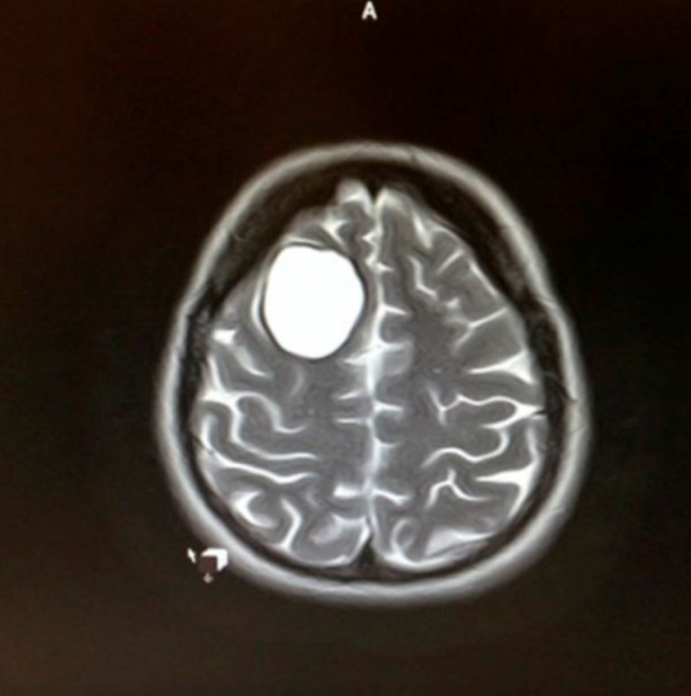

Βρήκαν το λόγο της κρίσης: είχε έναν όγκο σε μέγεθος μπάλας του γκολφ στο δεξί της ημισφαίριο.

Ο όγκος βρισκόταν εκεί για αρκετό καιρό, αλλά δεν είχε παρατηρήσει κάποιο σύμπτωμα.

Δεν είχε πονοκεφάλους, ζαλάδες ή προβλήματα με την όραση, οπότε έπρεπε τώρα να αντιμετωπίσει και αυτό, ενώ παράλληλα γεννούσε την κόρη της.